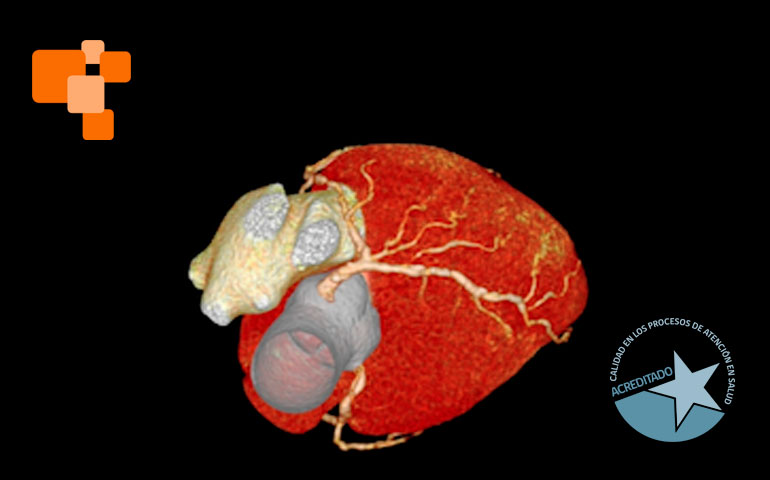

El TAC de calcio coronario es un examen de alta complejidad, realizado usualmente en centros de imagenología avanzada, mide el calcio en las arterias coronarias para evaluar el riesgo de eventos cardíacos futuros. Al proporcionar un score de calcio coronario, permite a los médicos identificar la acumulación de calcio y ajustar tratamientos para prevenir la aterosclerosis, una causa principal de ataques cardíacos. Según expertos, médicos especialistas en cardiologías lo sugieren principalmente para aquellos en riesgo moderado, pacientes que no han tenido síntomas, pero poseen factores de riesgo como hipertensión o colesterol alto.

La tomografía computada para el cálculo del score de calcio coronario permite identificar y cuantificar calcificaciones antes de que se manifiesten síntomas de enfermedad cardíaca, facilitando intervenciones tempranas. Es una técnica de diagnóstico por imagen que, a diferencia de otros métodos más invasivos, ofrece una evaluación rápida y no invasiva de las coronarias.

La elección de un centro de imagenología avanzada es crucial para asegurar la precisión del TAC de calcio coronario. En Centro de Diagnóstico San Lorenzo, nuestra infraestructura se encuentra equipada con la tecnología más avanzada, un TAC de 128 canales con inteligencia artificial, y todo un personal calificado que garantizan la calidad y fiabilidad de los resultados, aspectos fundamentales para un diagnóstico y tratamiento adecuado que recomendará su médico de cabecera.